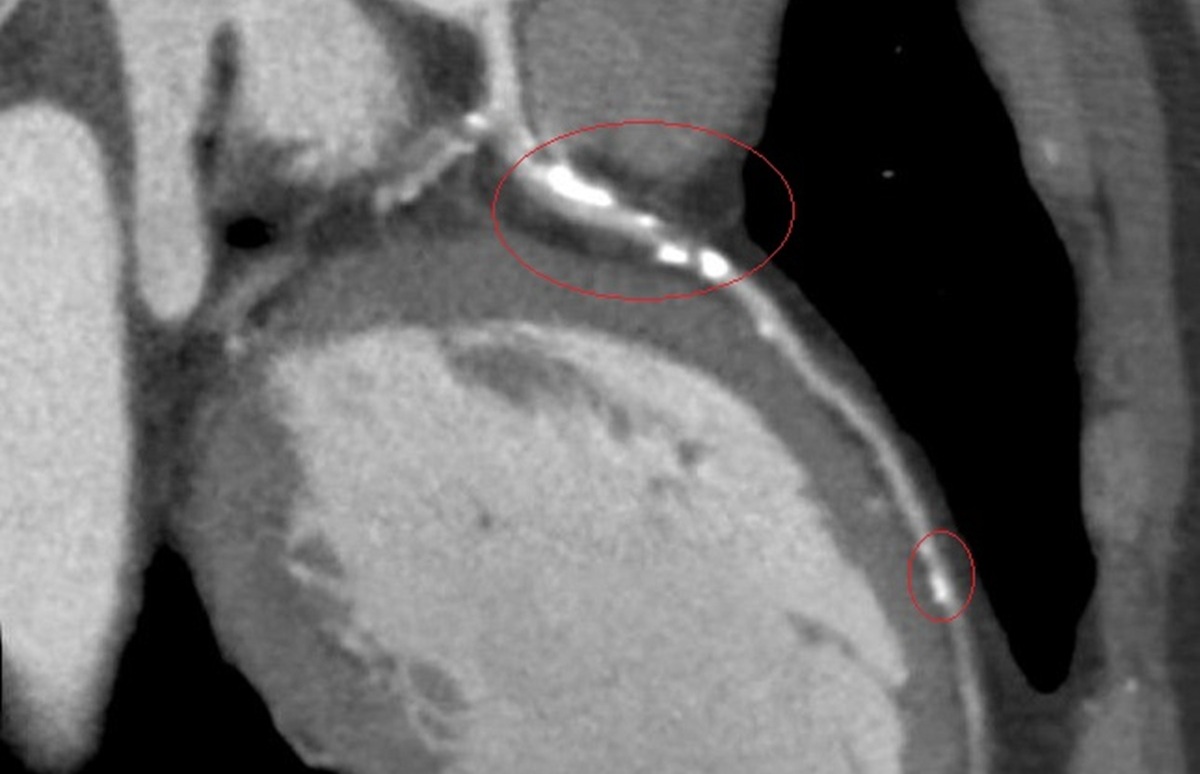

李學林說,醫療團隊透過心導管手術搭配 IVL技術,利用震波氣球貼近血管壁發出超聲壓力波,擊碎血管壁的堅硬鈣化斑塊,讓原本僵硬的血管恢復擴張性,為支架放置創造理想的環境,再植入3支支架,使支架能完整展開、貼合血管,降低支架血栓及再狹窄的風險。

▲李學林說,醫療團隊透過心導管手術搭配 IVL技術,利用震波氣球貼近血管壁發出超聲壓力波,擊碎血管壁的堅硬鈣化斑塊。(圖/彰化醫院提供)